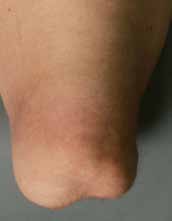

Bei der Operation selbst (Abb. 1–6) geht man so vor, dass zunächst ein zirkulärer Hautschnitt etwa 4 bis 7 cm unterhalb des Tibia-Plateaus erfolgt. Es ist besonders wichtig, darauf zu achten, möglichst viel Haut unterhalb des Gelenkspaltes zu belassen, weil in dieser Region die Haut sich erheblich retrahieren kann. Die Hautnaht muss aber unbedingt ohne Spannung erfolgen. Anschließend präpariert man am Patellaband hoch bis zum Gelenkspalt, eröffnet die Kapsel und durchtrennt dann sukzessive die Kreuzbänder und die Kapsel. Unter fortwährendem Zug am Unterschenkel wird sodann durch das Gelenk die Kapsel bis zur hinteren Kapsel durchtrennt. Dabei werden die auf der Knierückseite liegenden Strukturen geschont. Der Gelenkknorpel wird unberührt belassen. Die bradytrophen Menisci werden entfernt. Die Kniescheibe selbst wird nicht, wie immer wieder in Lehrbüchern beschrieben, an den Kreuzbandstümpfen fixiert, da hieraus oft eine Fehlpositionierung der Kniescheibe unter die Belastungsfläche resultiert. Die Kniescheibe ist in dieser Position nicht endbelastbar, sie verursacht Druckprobleme (s. Abb. 11) und schmerzt. Zudem resultiert hieraus eine Verlängerung des Stumpfes.

Das knöcherne Stumpfende wird von den Oberschenkelrollen gebildet; diese sind voll endbelastbar. Sie werden nicht durch Anteile der Wadenmuskulatur gedeckt; hieraus würde ansonsten wieder eine Überlänge resultieren. Zudem ist zu vermuten, dass, falls die Unterschenkelmuskulatur noch vital um das Stumpfende herumgelegt werden könnte, eine Unterschenkelamputation mit kurzem Stumpf möglich gewesen wäre, die funktionell der Knieexartikulation in der Regel überlegen ist. Ist nicht genügend Haut zur spannungsfreien Deckung vorhanden, ist eine Möglichkeit zur Hautspannungsentlastung die Entfernung der Kniescheibe. Diese muss allerdings immer mit einer Synovialektomie im oberen Gelenkrezessus kombiniert werden, um Synovialitiden und Synovialfisteln zu vermeiden. Falls die lokale Durchblutung der Haut keinen sagittalen Schnitt zulässt, sind auch Schnittführungen mit langem Hinteroder Vorderlappen möglich. Die spannungsfreie Deckung mit vitaler Haut hat absoluten Vorrang.

Der direkten postoperativen Nachbehandlung (Abb. 7 u. 8) kommt eine besondere Bedeutung zu. Nach der Amputation kommt es spontan – wie auch beim entspannten Liegen – zu einer Außenrotationslage des Beines. Hierdurch liegt der laterale Femurkondylus dann direkt auf der Bettauflage auf. In der frühen postoperativen Phase kann es leicht zu Drucknekrosen kommen, die das Operationsergebnis zunichtemachen. Oft reibt („shivert“) der Patient mit dem Stumpf in der Aufwachphase auf der Bettoberfläche; teilweise versucht er, sich mit dem Stumpf beim Aufrichten auf dem Bett abzustützen. Daher muss bei der postoperativen Verbandtechnik die Druckreduktion in diesen Bereichen durch Wattewickel garantiert werden (s. Abb. 7); der Operateur muss sich nach der Operation noch am OP-Tag darüber vergewissern.